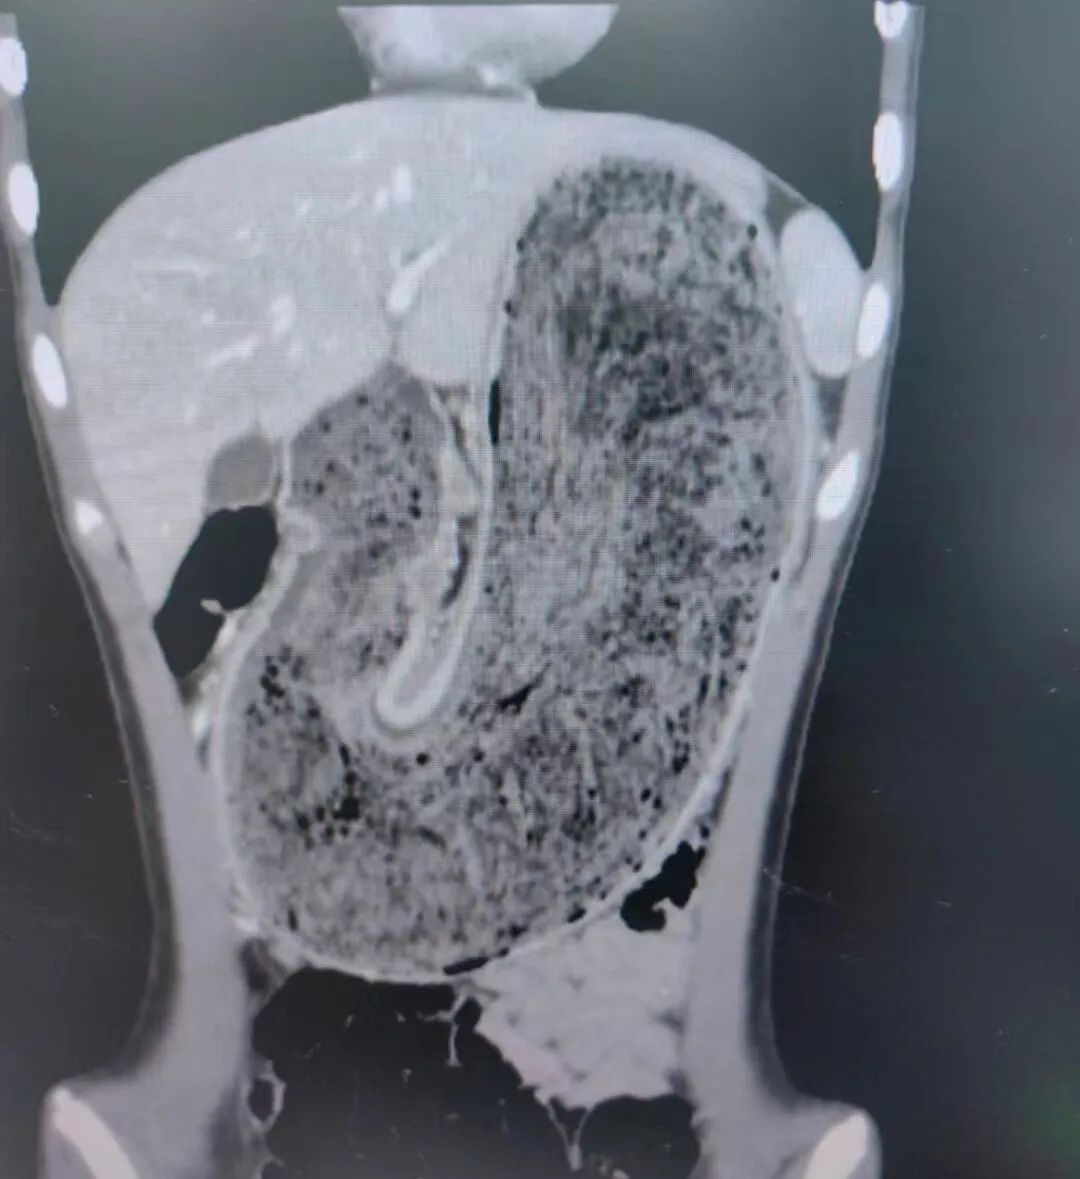

▲欢欢的胃腔里有大块的毛絮状结石

随后,他们将女儿送到东莞市妇幼保健院。内科医生张铭承接诊后对欢欢进行检查,结果惊讶地发现,欢欢的胃腔和肠管里有大块的毛絮状结石,几乎占据整个胃部——这就是腹痛的根源。

东莞市妇幼保健院小儿外科主任伍岗泉主刀,他带领团队耗时近60分钟,将长38厘米×宽15厘米×厚10厘米的毛发结石从欢欢胃部成功取出。欢欢的毛发胃石巨大,严重影响进食和生长发育,通过手术,欢欢腹痛消除,恢复良好。